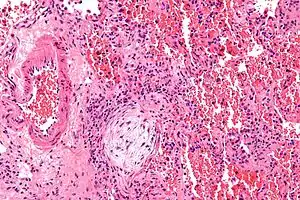

| Micrograph showing a Masson body (off center left/bottom of the image – pale circular and paucicellular), as may be seen in cryptogenic organizing pneumonia. The Masson body plugs the airway. The artery associated with the obliterated airway is also seen (far left of the image). H&E stain. | |

Biopsy findings in patients with organizing pneumonia consist of loose connective tissue plugs involving the alveoli, alveolar ducts and bronchioles. The loose connective tissue plugs occupying the alveolar spaces often connect to other connective tissue plugs in nearby alveoli via the pores of Kohn creating a characteristic butterfly pattern on histology.[9] There is usually minimal to no interstitial inflammatory changes in biopsies of organizing pneumonia.[9]

Histologically, cryptogenic organizing pneumonia is characterized by the presence of polypoid plugs of loose organizing connective tissue (Masson bodies) within alveolar ducts, alveoli, and bronchioles.